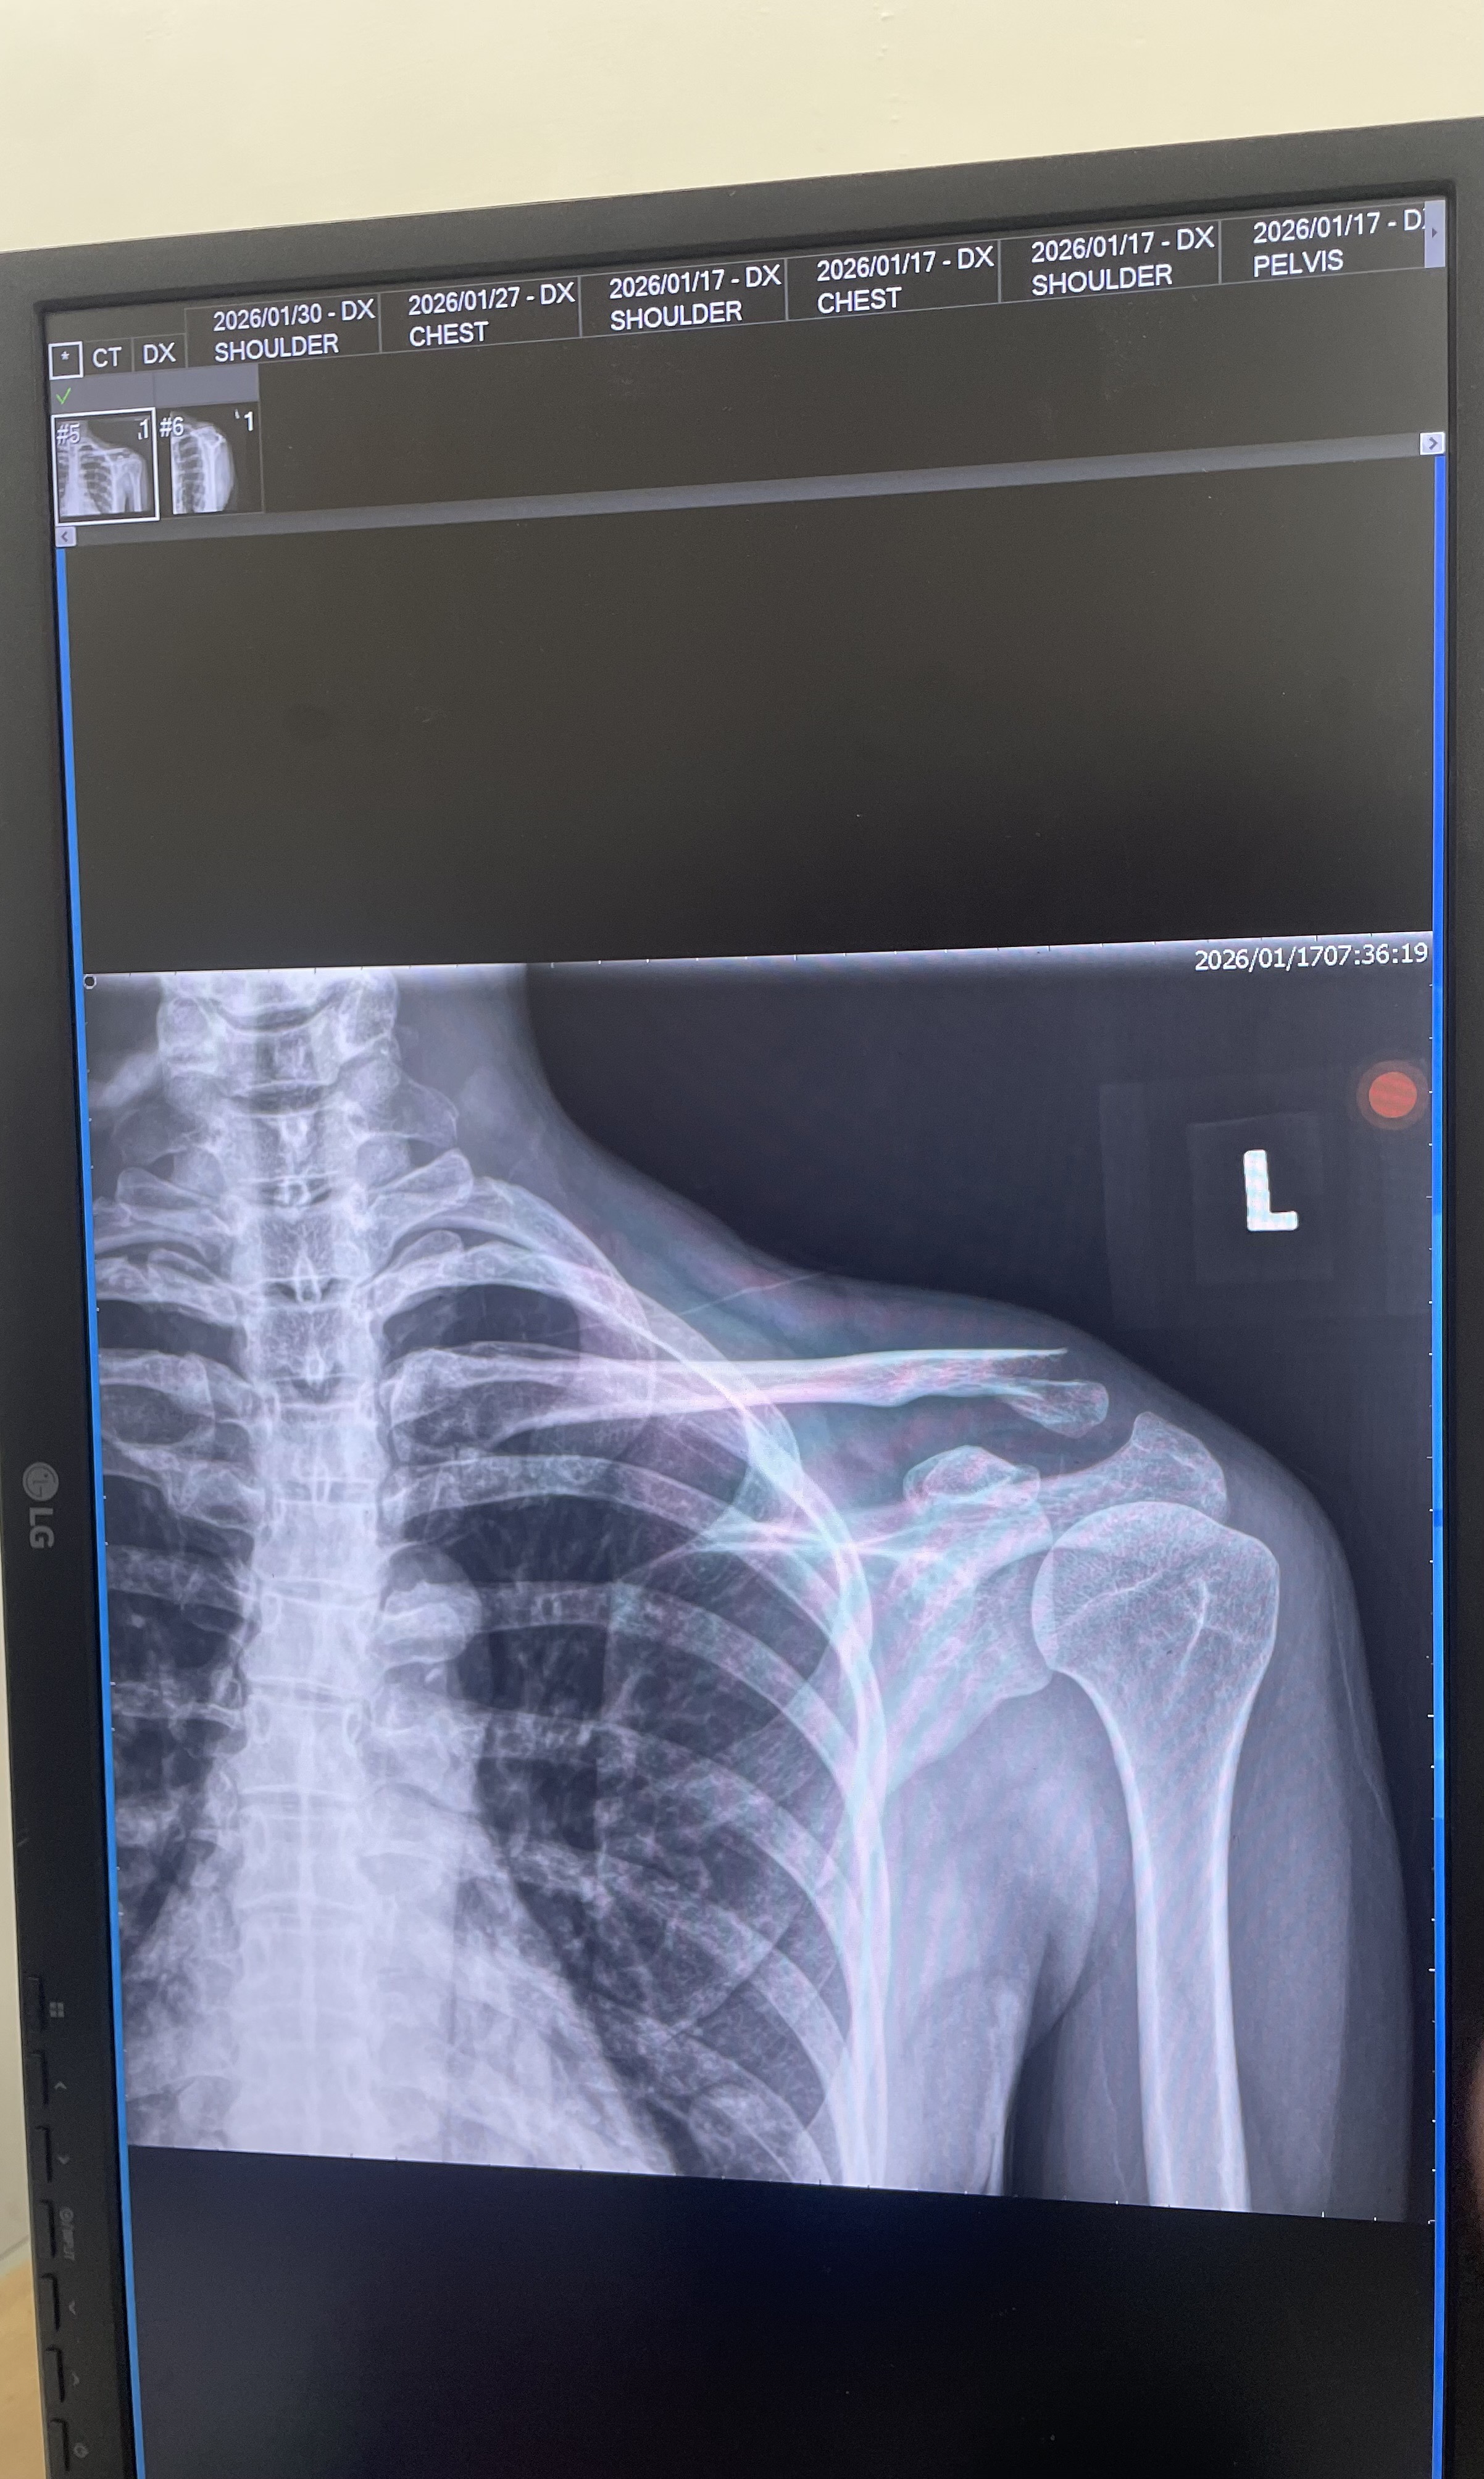

左側遠端鎖骨位移性骨折,手術植入鈦金屬骨板,恢復需一年以上

手術 左側遠端鎖骨骨手術復位併鈦合金五爪式解剖型勾行鋼板內固定